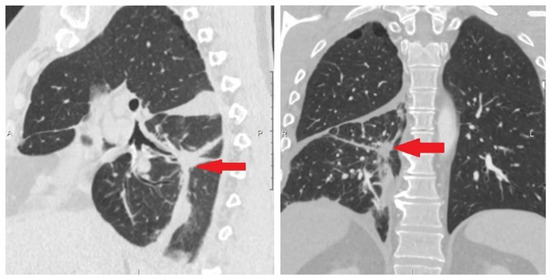

3.6.1. A Clinical Example Demonstrating a Favorable Outcome of the Disease and the Evolution of the Number of CTCs Detected in the Peripheral Blood